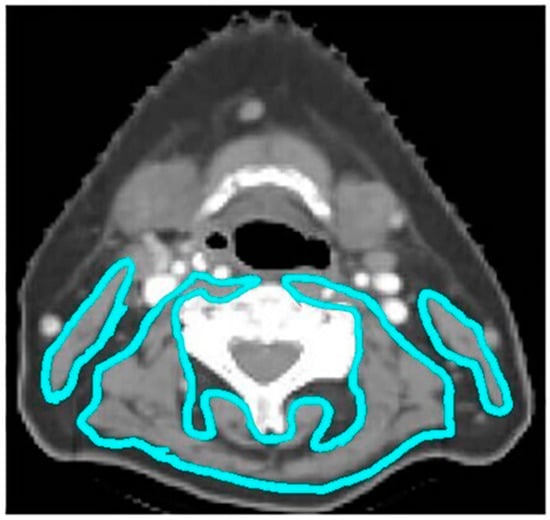

Thirty-four percent of patients experienced at least one missed radiation day due to toxicity, with a median of two treatments missed (range, 1–30). On UVA, Older patients required more radiation treatment breaks compared to younger patients (51.0% versus 29.9%, p < 0.01) (Table S1). MVA to identify factors associated with at least one radiation treatment break (Table 2) found only age ≥70 as a predictor (p = 0.012). Twelve percent of patients required a prolonged radiation treatment break, defined as a break of 1 week or greater. The most common reason for prolonged break was CTCAE grade 3 mucositis (36.3%). Older patients were more likely to require prolonged treatment breaks than younger patients on UVA (27.5% versus 8.6%, p < 0.01) (Table S1). On MVA (Table 2), age ≥70 (p < 0.01), low albumin status (p = 0.03), and sarcopenia (p = 0.04) were identified as predictors of prolonged radiation treatment breaks. Representative CT slices comparing radiation toxicity of an older adult with sarcopenia and younger adult without sarcopenia are shown in Figure 2. Nutritional dependence on PEG tube (CTCAE grade 3) was similar between groups (65.6% younger versus 66.7% older, p = 0.89). One-hundred six patients lost greater than 10% of their pretreatment body weight (42.5% younger versus 23.5% older patients, p = 0.012). Patients requiring hospital admission (CTCAE grade 3) during treatment occurred in 68 total patients (25.0%), with a trend toward older patients (35.3% versus 22.6%, p = 0.060).

Figure 2. A comparison of older and younger patients with and without sarcopenia with similar BMI. The left panel represents a 70-year-old man with HPV-positive oropharynx cancer with sarcopenia (BMI 27.6 kg/m²) experiencing 10 days of radiation treatment delay, while the right panel represents a 56-year-old man with HPV-positive oropharynx cancer without sarcopenia (BMI 26.7 kg/m²) having no days of radiation treatment delay.